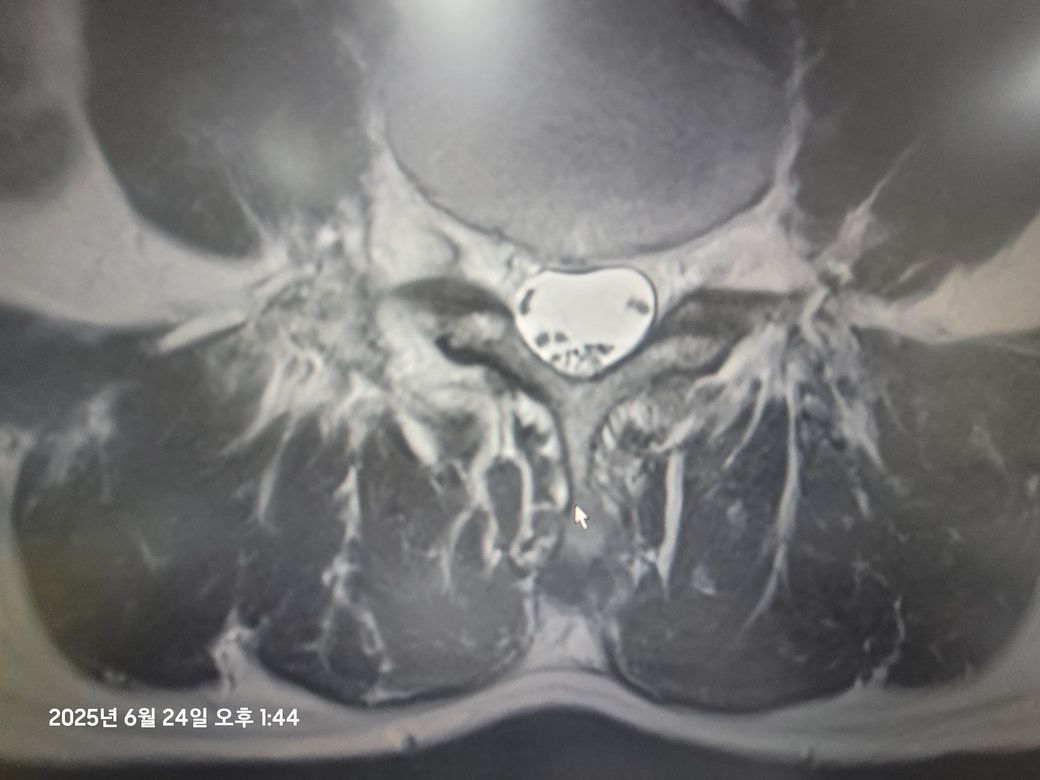

정형외과 에서 5번 디스크 탈출 진단 받았습니다

의사 선생님이 심각한 상황이라며 수술을 빨리해야 한다고 합니다.

지금 증상은 진단후 10일 정도 지난 상황이며 그 동안 하루 두시간 걷기운동으로 방사통은 많이 잡은 상태이며 발등 들기가 좀 힘들고 엄지 발가락이 잘 움직이지않고 한쪽 다리가 반대쪽 다리에 비해서 힘이 좀 빠져있는 상태 입니다(처음에는 걸을때도 통증과 힘빠짐 으로 걷기도 힘들었는데 현재는 걷는것은 아무문제 없습니다)

제가 걱정하는 것은 디스크수핵이 신경을 압박하고 있는 것인데요 저는 정말로 수술은 피하고 싶습니다 하지만 수술하지 않을경우 신경에 영구손상을 입을수도 있다고 하는데요 전문가의 조언을 듣고 싶습니다.

• 1번 째 사진